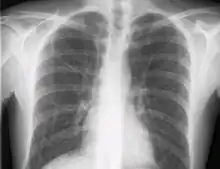

Le contrôle radiologique de la position de la voie doit être fait par une radiographie du thorax.

Le cathétérisme de la veine sous-clavière s'effectue dans des conditions d'asepsie chirurgicales. Pour un opérateur droitier, la veine sous-clavière gauche est la plus accessible. L'aiguille est introduite sous la clavicule, à la distance de deux travers de doigt du sternum en direction de l'épaule opposée. La main droite de l'opérateur introduit l'aiguille pendant que la gauche détermine les reliefs osseux par palpation. De la même manière, un guide est introduit par l'aiguille dès que la veine est cathétérisée. Le guide sert de tuteur à l'introduction de la voie. Cette dernière est fixée à la peau par suture. Un contrôle radiologique de la position de la voie est effectuée afin de ne pas laisser l'extrémité de la voie toucher les cavités cardiaques. On vérifie par le même examen l'absence de pneumothorax.